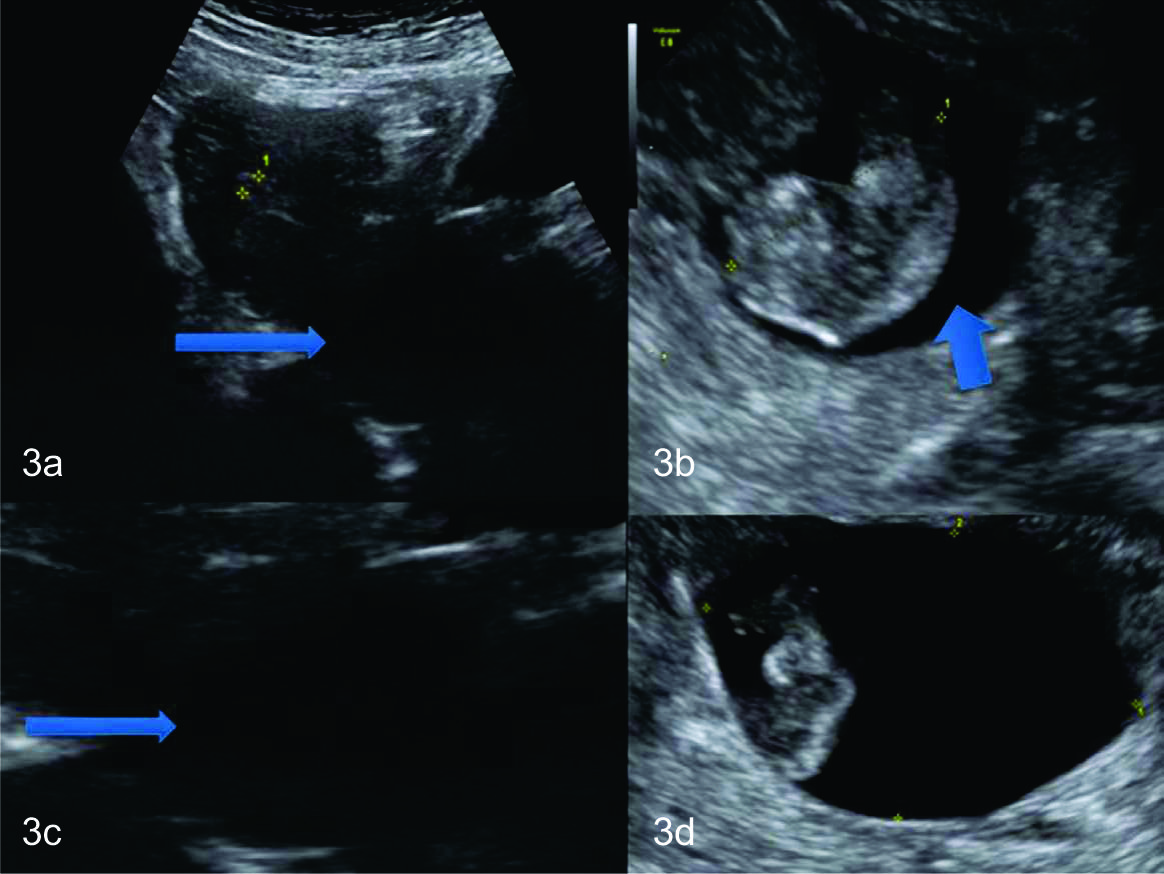

Figura 5

Emabarazo normal

Una de nuestras pacientes, meses después del procedimiento, que llegó a término sin complicaciones.